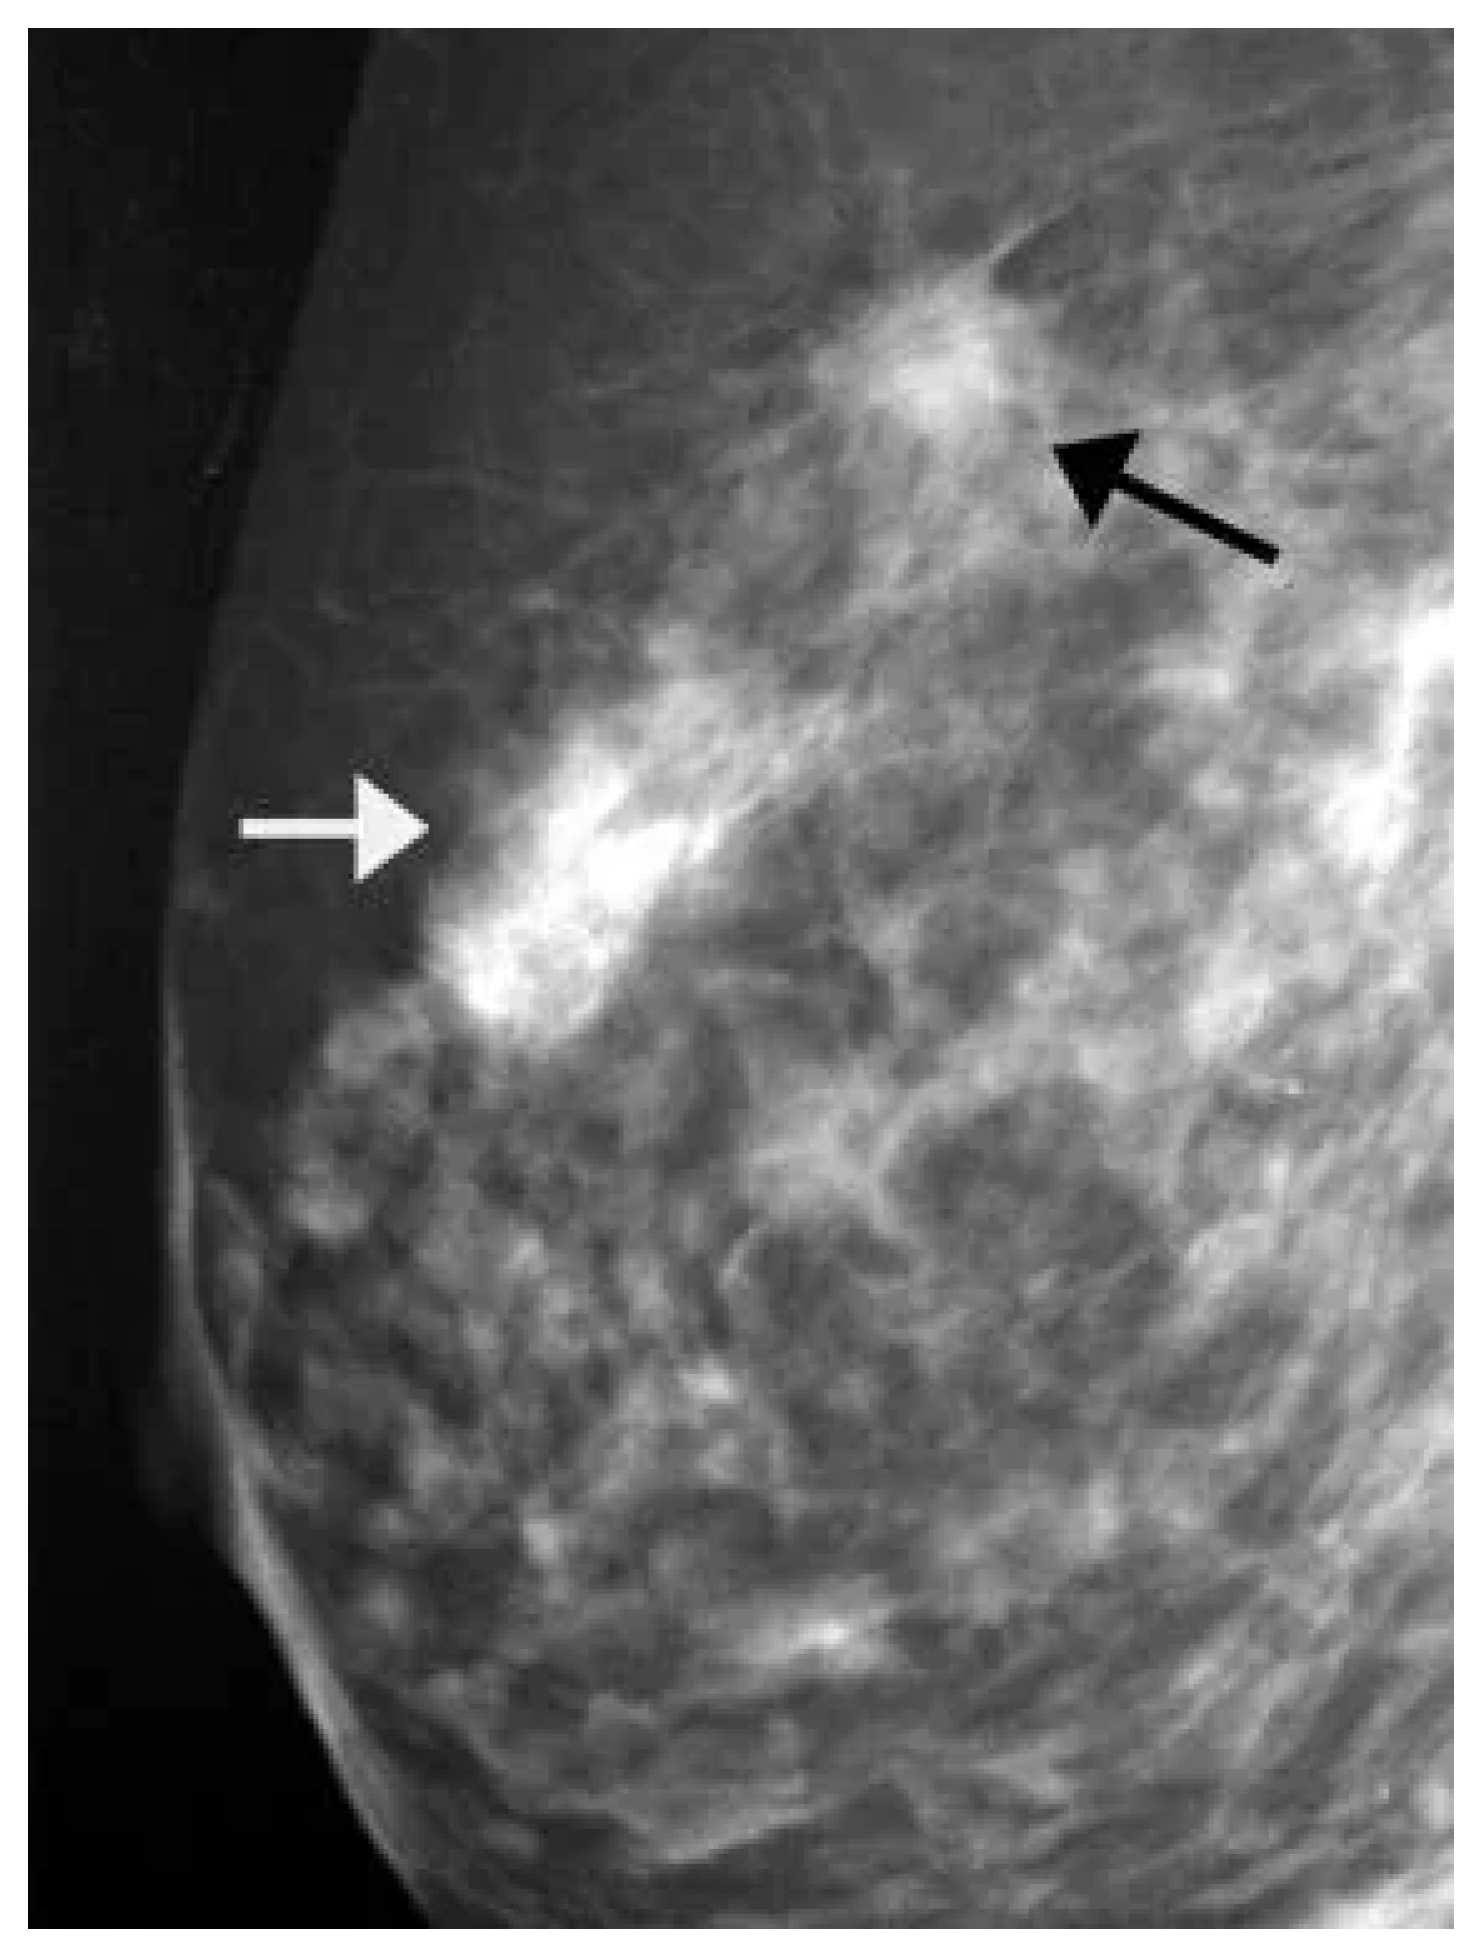

8.3. Breast Cancer Detection Based on Magnetic Resonance Imaging (MRI) Images

Magnetic resonance imaging (MRI) is a safe, non-invasive technique that uses magnetic fields and radio waves to produce detailed internal body images. MRI is employed in the diagnosis and monitoring of conditions such as soft tissue abnormalities, tumors, and brain and spinal disorders. This section highlights AI-based methods for BC detection using MRI images [115]. Figure 17 displays a sample MRI image with a highlighted area, marked by the red arrow, indicating a potential abnormality for further examination.

Figure 17.

A sample MRI image [92,116].